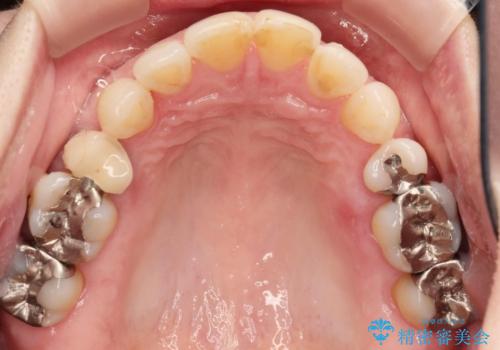

口の中の金属を外したい セラミッククラウンによる治療

- 笑った時に口の中で目立つ金属を外したい、虫歯の治療を再発の内容しっかりと行って欲しいと希望され来院されました。

銀歯・虫歯を丁寧に除去したのち精密なセラミック治療を行うことで長期的な予後を目指します。